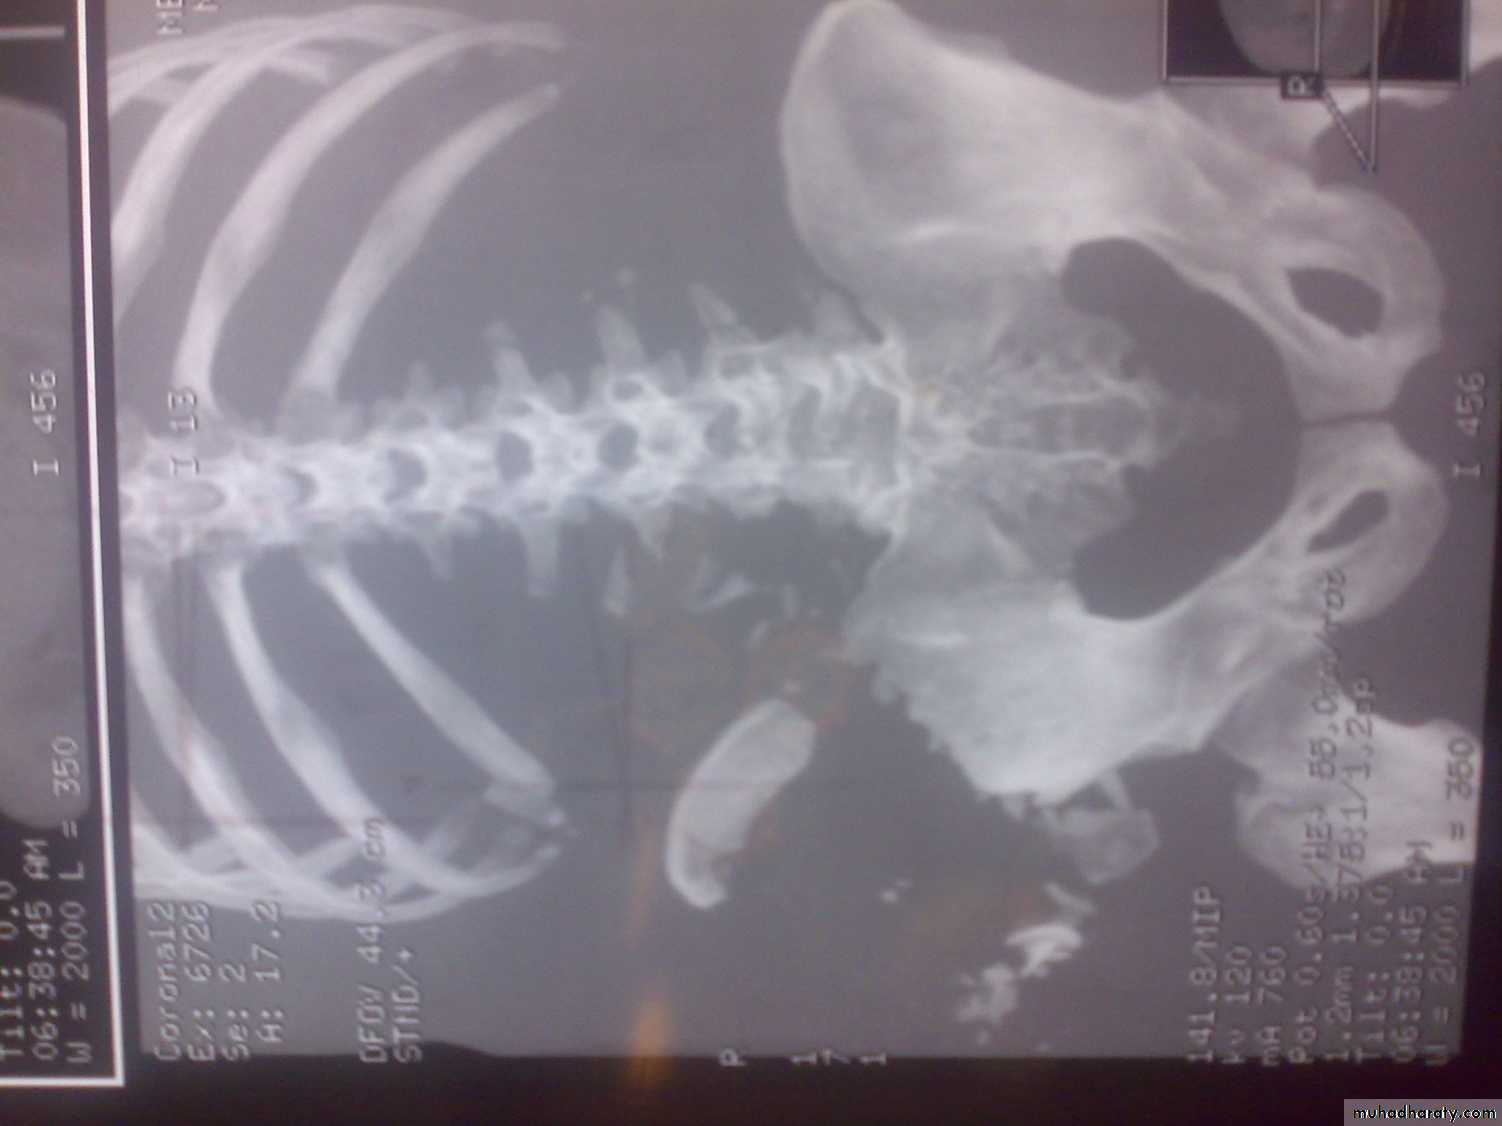

3-D reconstructed images.

3-D C-T in fracture pelvic ilium